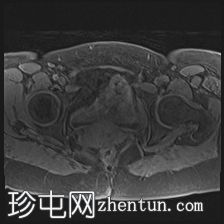

MRI

轴位

可见膀胱左侧壁有一边界清晰的T2低信号实

性病

灶,无扩散受限,均匀强化。未见膀胱周围侵犯或肾积水。

子宫底部前壁可见一小肌瘤。双侧卵巢可见无强化囊肿。盆腔及腹股沟未见异常淋巴结肿大。

这是一例经组织学证实的膀胱平滑肌瘤病例。